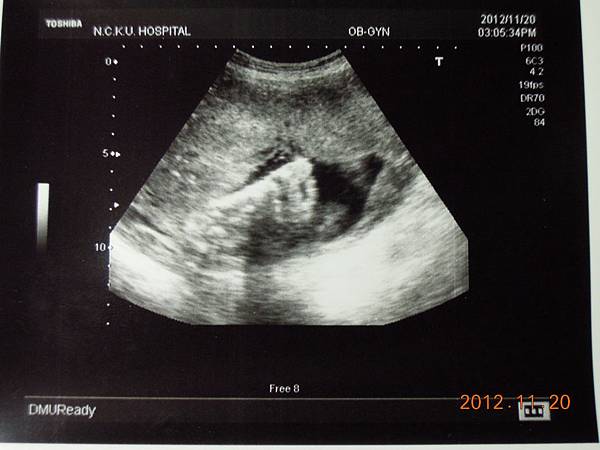

2012-11-20 第十次產檢(38W)